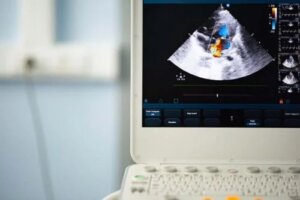

În timpul controlului, ar putea folosi un stetoscop pentru a putea auzi bătăile neregulate ale inimii și, de asemenea, pentru a analiza semnele de murmur cardiac. După aceea, pentru a verifica dacă valvă aortică este bicuspidă, va face o ecocardiogramă care îl va ajuta să evalueze cum funcționează inima.